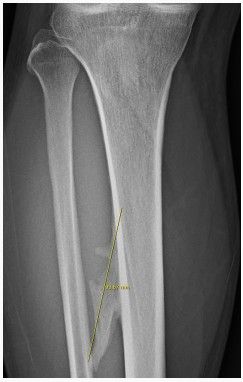

동네병원에서 우연히 찍었는데 양쪽 정강이에 종양이 있다고 합니다 크기는 오른쪽 기준 9~10센치 정도구요

골연골증이나 경비결합외골증??? 이라는데 선생님들 한번 봐주세요 혹시 MRI찍어야 되나요?

골연골종이나 경비결합외골증 진단을 받았다면 양성 종양일 가능성이 큽니다 크기가 9~10cm라면 추가 검사를 위해 mri촬영이 필요할 수도 있으니 정형외과 전문의와 상담해보시는 것이 좋습니다 특히 통증이 있거나 크기가 계속 커진다면 정밀 진단이 중요합니다!